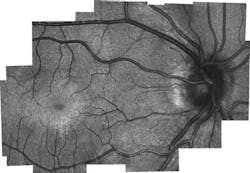

The new device was then given to clinicians for testing on adults, which proved that it was capable of getting accurate photoreceptor density information. It was also used for research imaging in children who were already having an eye exam under anesthesia.

"But because children have never been imaged with these systems before, there's no gold standard that we can compare it to," LaRocca explains. "The results do, however, match theories of how cones migrate as the eye matures. The tests also showed different microscopic pathological structures that are not normally possible to see with current lower-resolution, clinical-grade handheld systems."